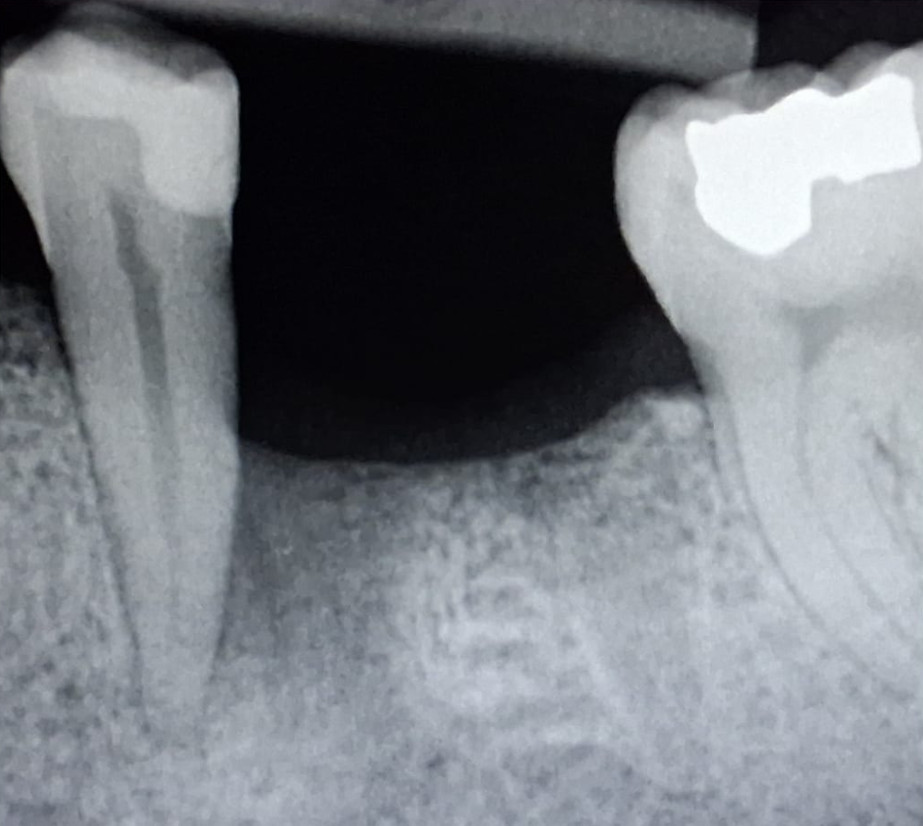

Quando manca uno o più denti non si fa più ricorso ai classici “ponti” che prevedono

l’utilizzo come pilastri di sostegno di denti naturali sacrificati allo scopo.

Ormai da molti anni (circa 35) dove manca un dente si inserisce una radice artificiale

(impianto) su cui successivamente, viene posizionata una corona (capsula).

Prima